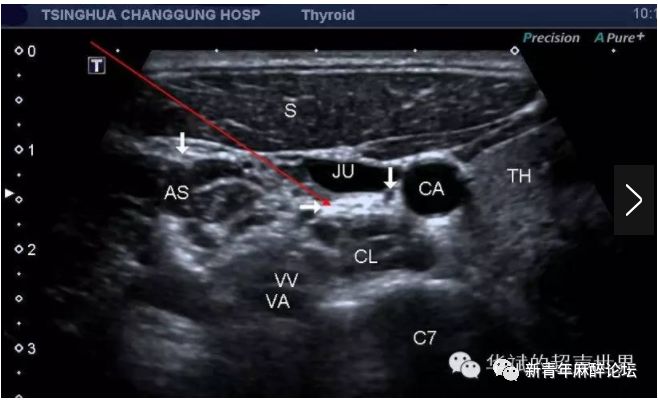

图2超声引导第七颈椎水平超声图像(引自:张华斌华斌的超声世界)

(图2第七颈椎横突水平横断。TH:甲状腺,CL:颈长肌,C7:第六颈椎,CA:颈总动脉,JU:颈内动脉,AT:第6颈椎横突前结节,PT:第6颈椎横突后结节,AS:前斜角肌,S:胸锁乳突肌,VV和VA:椎动脉和椎静脉。左边箭头:膈神经,右边箭头:迷走神经。水平箭头:星状神经节。)

由上图可见,这一断面可以清晰显示位于颈动脉鞘(其内有颈总动脉、颈内静脉和迷走神经)和颈长肌之间的星状神经节(位于颈长肌表面,椎前筋膜深面),显现为高回声的筛网状结构。同时可见星状神经节周围有许多血管神经结构。

正是由于超声能够清晰分辨星状神经节的结构,因此目前的星状神经节阻滞一般都是在超声引导下施行,能够做大程度地避免并发症的发生,同时由于定位准确,能够利用较少的药量就能达到满意的效果。

超声引导下星状神经节阻滞选择C7横突所示的断面,由外侧入路(即图中红色长箭头所示),药液注射于星状神经节周围。操作前年务必打开超声多普勒或血流确认椎动脉/静脉位置,以免穿刺针刺破椎动静脉造成局部血肿,严重者误入局麻药,药液随椎动脉直接入脑,导致局麻药中毒,抢救非常棘手。成功的星状神经节阻滞后患者会出现典型的Horner征的表现,即:眼睑下垂、面色潮红无汗、瞳孔缩小等。